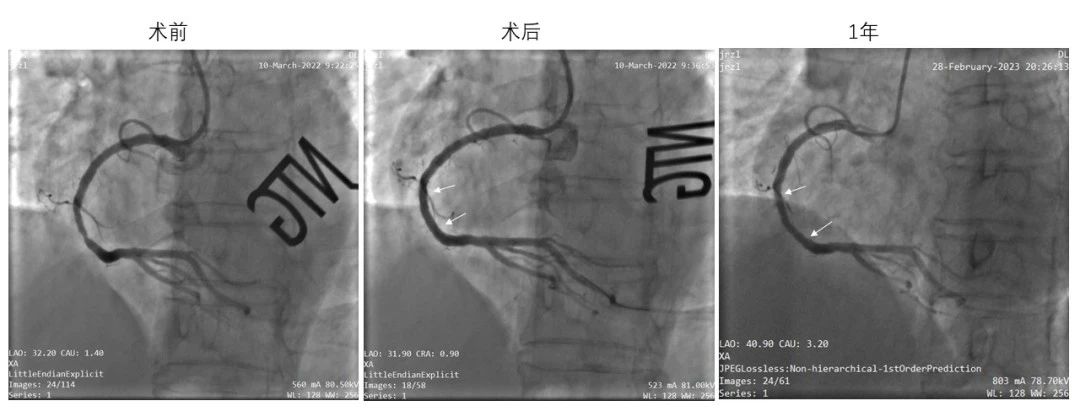

(左:术前靶病变处造影;中:IBS?支架植入后造影;右:术后1年造影,了局显示支架内畅达,未见显著狭幼)

IBS?冠脉支架的可行性临床钻研(FIM,即I期临床钻研)于2018年起头受试者入组,目前已顺利实现4年随访,了局批注其在单一原发性冠脉病变中拥有优良的中期安全有效性。血管造影(QCA)及血管内光学有关成像(OCT)丈量显示,IBS?冠脉支架植入6个月后靶病变均匀管腔面积略有增大的趋向,注明IBS?冠脉支架逐步降解后可能会对血管带来正向沉塑,从而有望真正体现“染指无植入”的理想和优势。